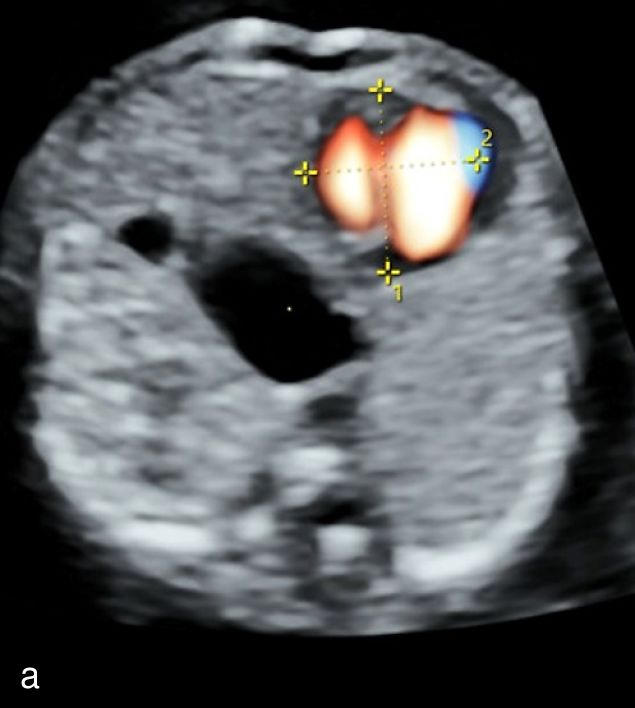

8

Ultrasound imaging of right-sided aortic arch at 12+3 weeks’ gestation using color Doppler (a) and spatiotemporal image correlation (b) modes.